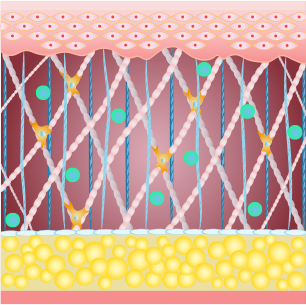

섬유아세포가 대사활동을 하는 동안 섬유아세포에 자극을 주어

콜라겐을 생성하거나, 콜라겐이 서로 합성되는 현상이 일어납니다.

탄력 개선